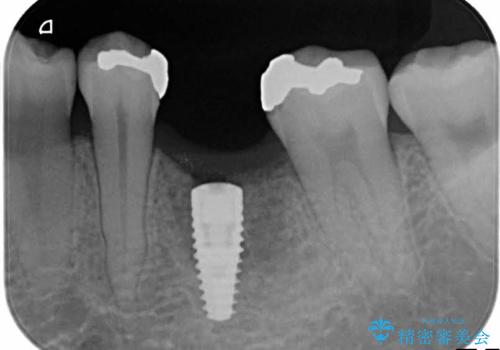

- 治療計画

- 保存不可能な歯の抜歯後、待時にてインプラントを埋入、2回法にて咬合回復を計画した。

同時に、前後の歯の金属のやり直しも行った。

インプラントの種類:strauman SLActive

かぶせ物の種類:Bellezza screw retain